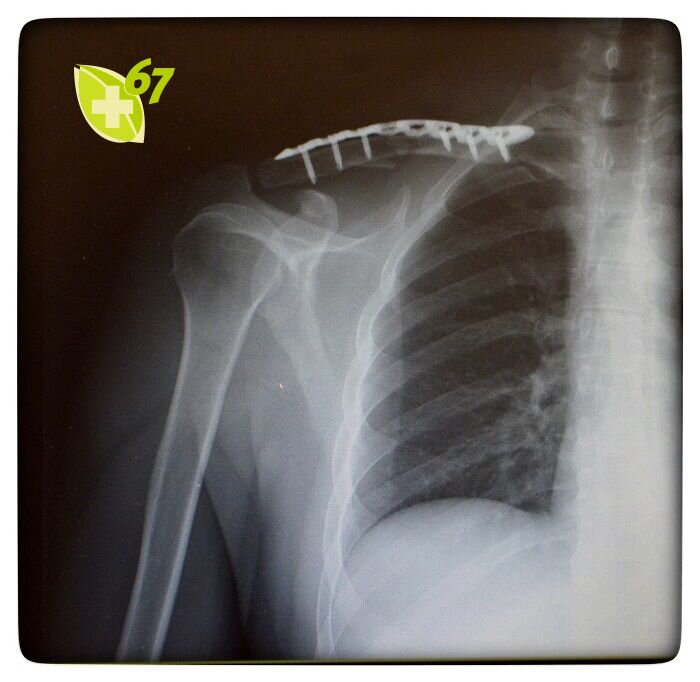

Скорая помощь 🚑 доставила мужчину в приемное отделение нашей больницы. По результатам рентгенологического исследования у пострадавшего был диагностирован закрытый оскольчатый перелом правой ключицы.

В рамках операции врачами была выполнен накостный остеосинтез ключицы - элементы поврежденной кости были зафиксированы с помощью специальной пластины с угловой стабильностью. Операция заняла 40 минут.